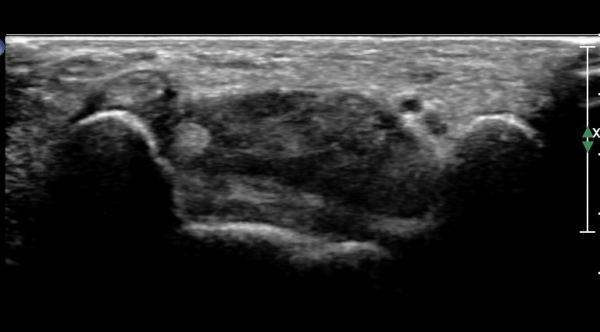

ÆÄ¿öµµÇ÷°¸Ó»ç»ó Ç÷·ùÁõ°¡´Â °üÂûµÇÁö ¾Ê´Â´Ù(»çÁø 4).